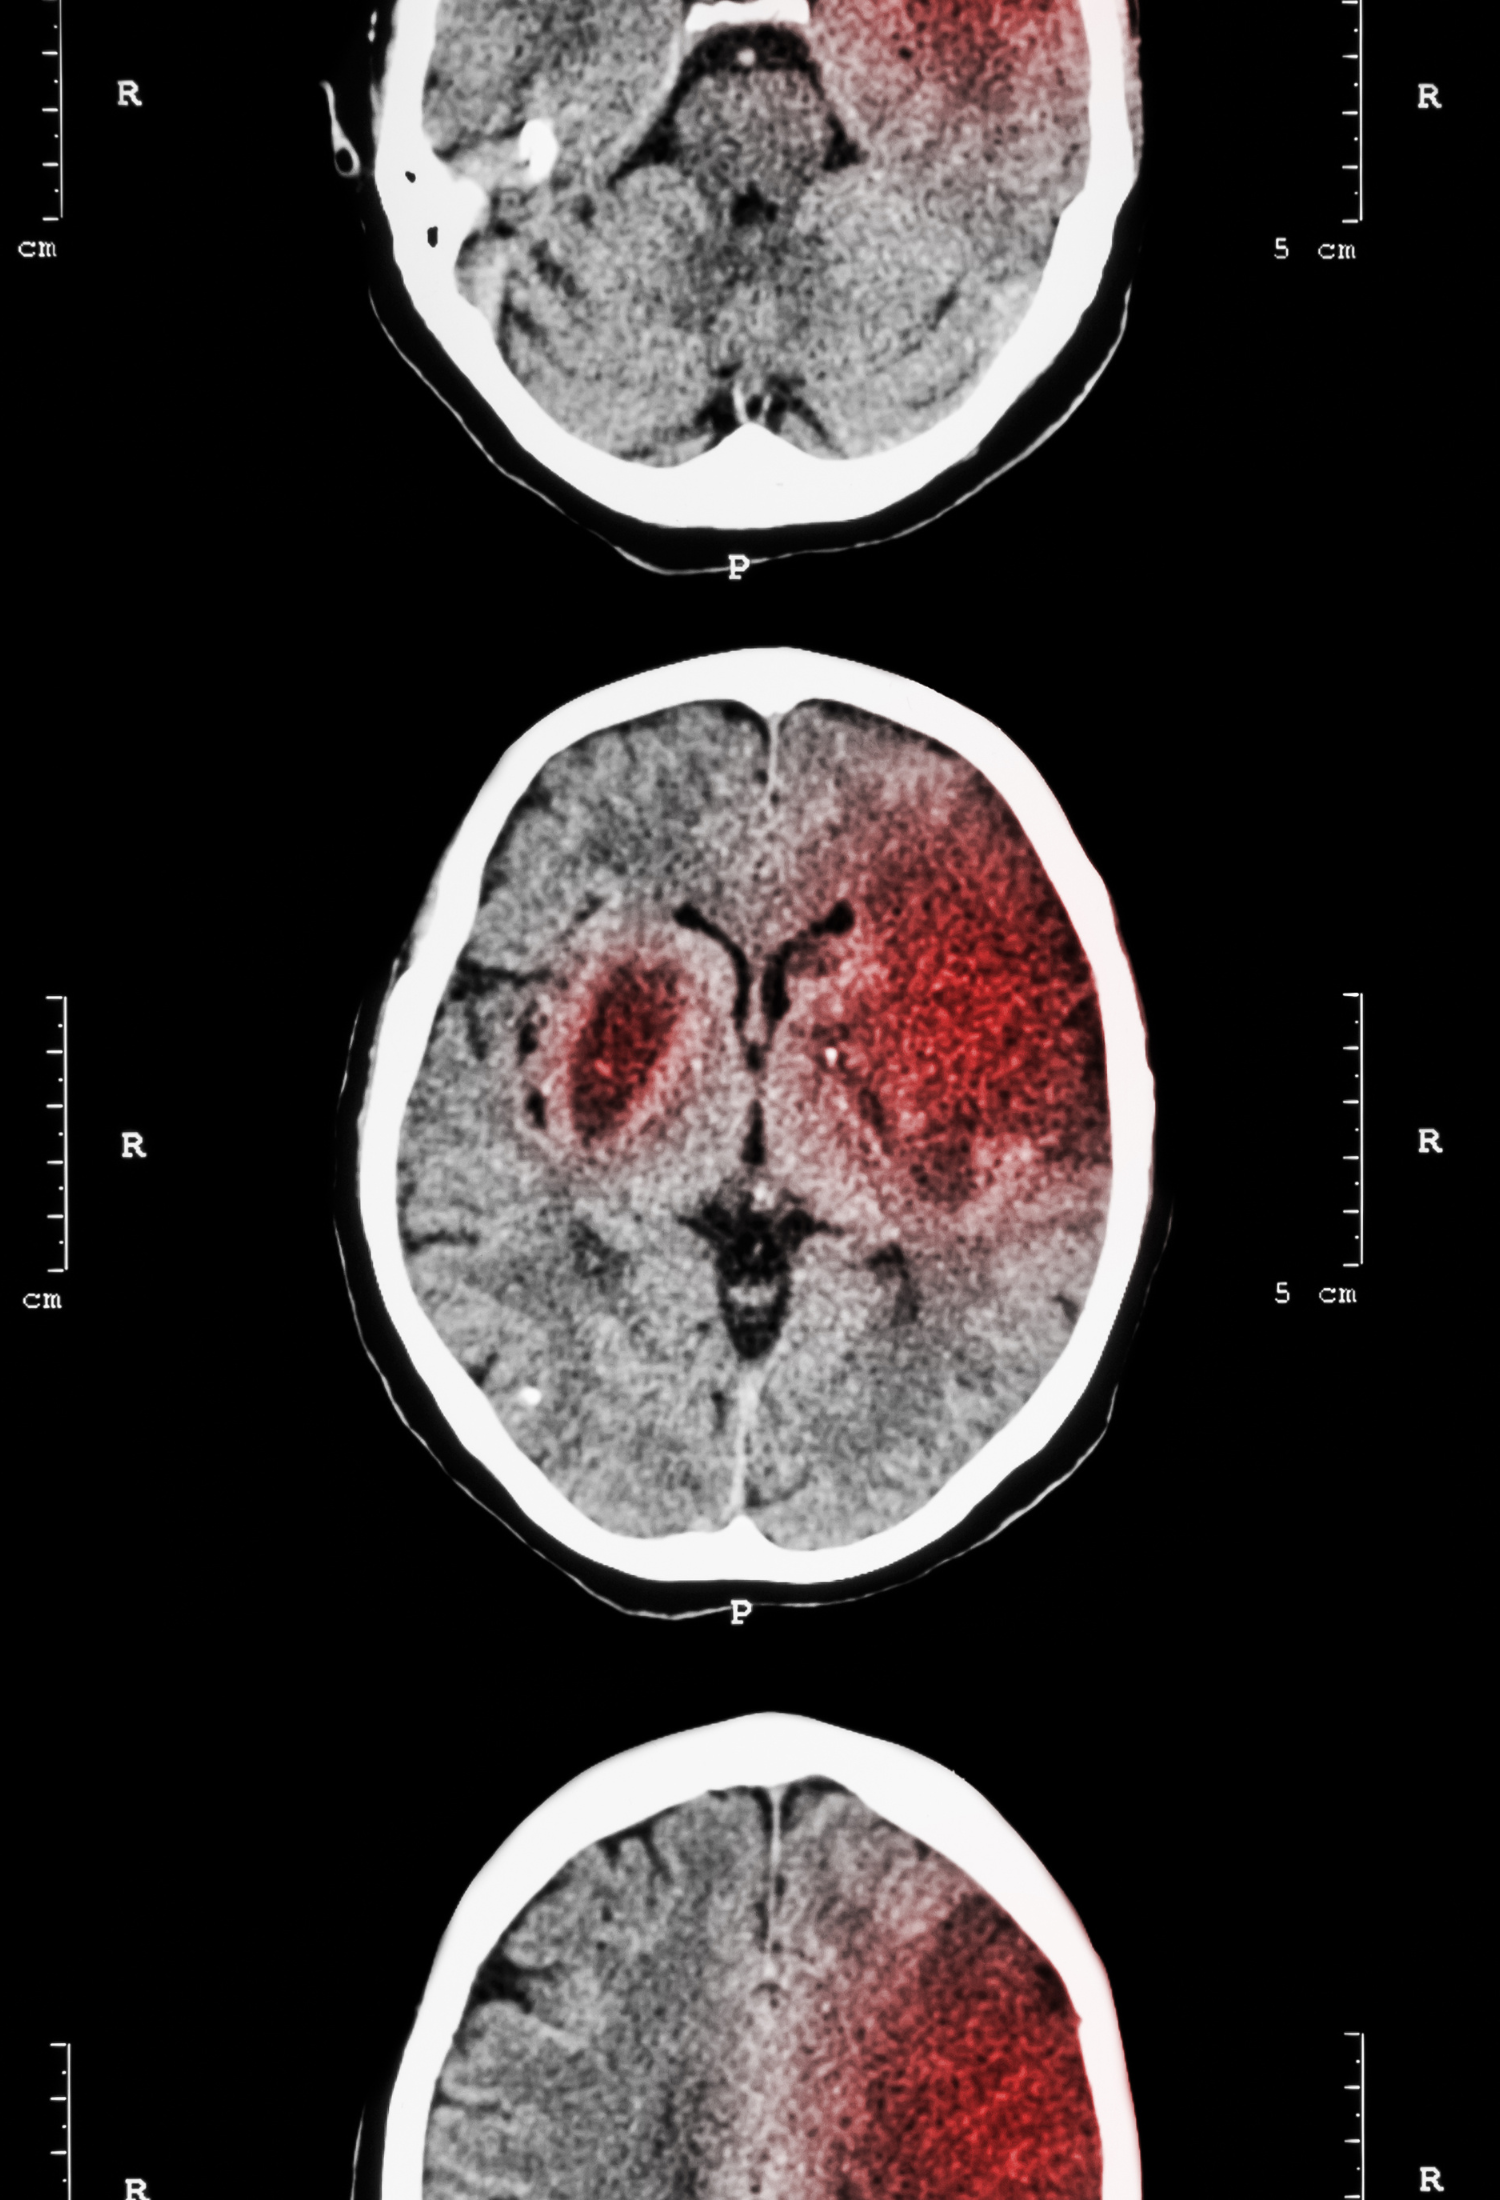

They are currently working to define the nature of, and causal relationships between, SCRD, neurodegenerative disease, pain and stroke.

A transatlantic research network was awarded $7million to investigate the interactions between the biology of the body’s internal clock and disordered physiological processes associated with stroke.

Aiming to identify novel targets for stroke therapy based on circadian biology, the European part of the network is coordinated by the Radcliffe Department of Medicine’s Professor Alastair Buchan.

Professor Buchan is working closely with Professors Russell Foster and David Ray from the Sleep and Circadian Neuroscience Institute (SCNi), as the network generates new knowledge with the potential to advance the diagnosis, prevention and treatment of cardiovascular and neurovascular disease.